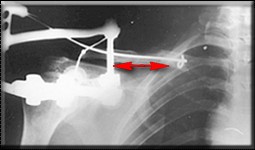

Идеальным вариантом представляется резекция ложного сустава, замещение образовашегося дефекта васкуляризированным малоберцовым трансплантатом и интрамедуллярный блокированный остеосинтез.

В условиях российской бедности мы делали свободным "столбиком" из малоберцовой и неблокированным штифтом. Результат был хороший (фото).